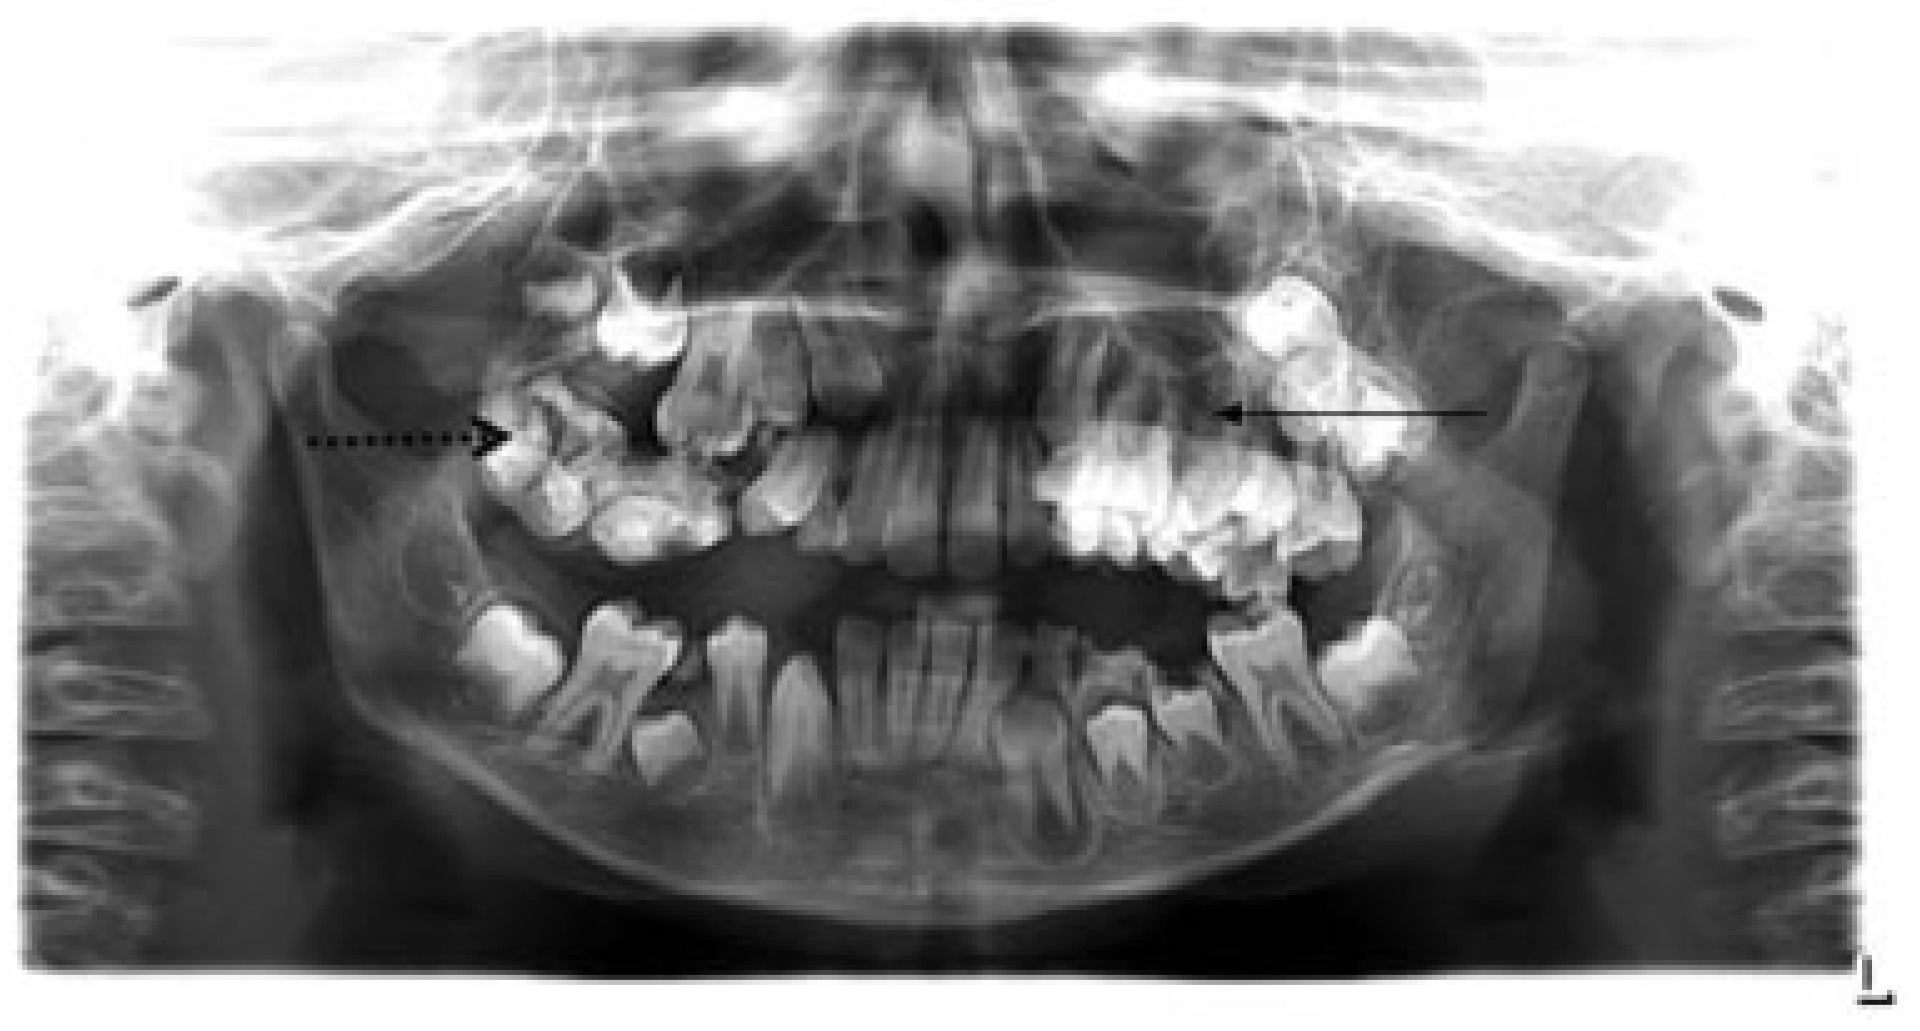

A Rare Case of Multiple Oblique Facial Clefts with Supernumerary Teeth: Case Report

- Incomplete Tessier 7 soft tissue facial cleft and a complete skeletal Tessier 7 cleft on the right side

- Incomplete Tessier 5 skeletal and soft tissue Tessier 6 facial cleft on the left side